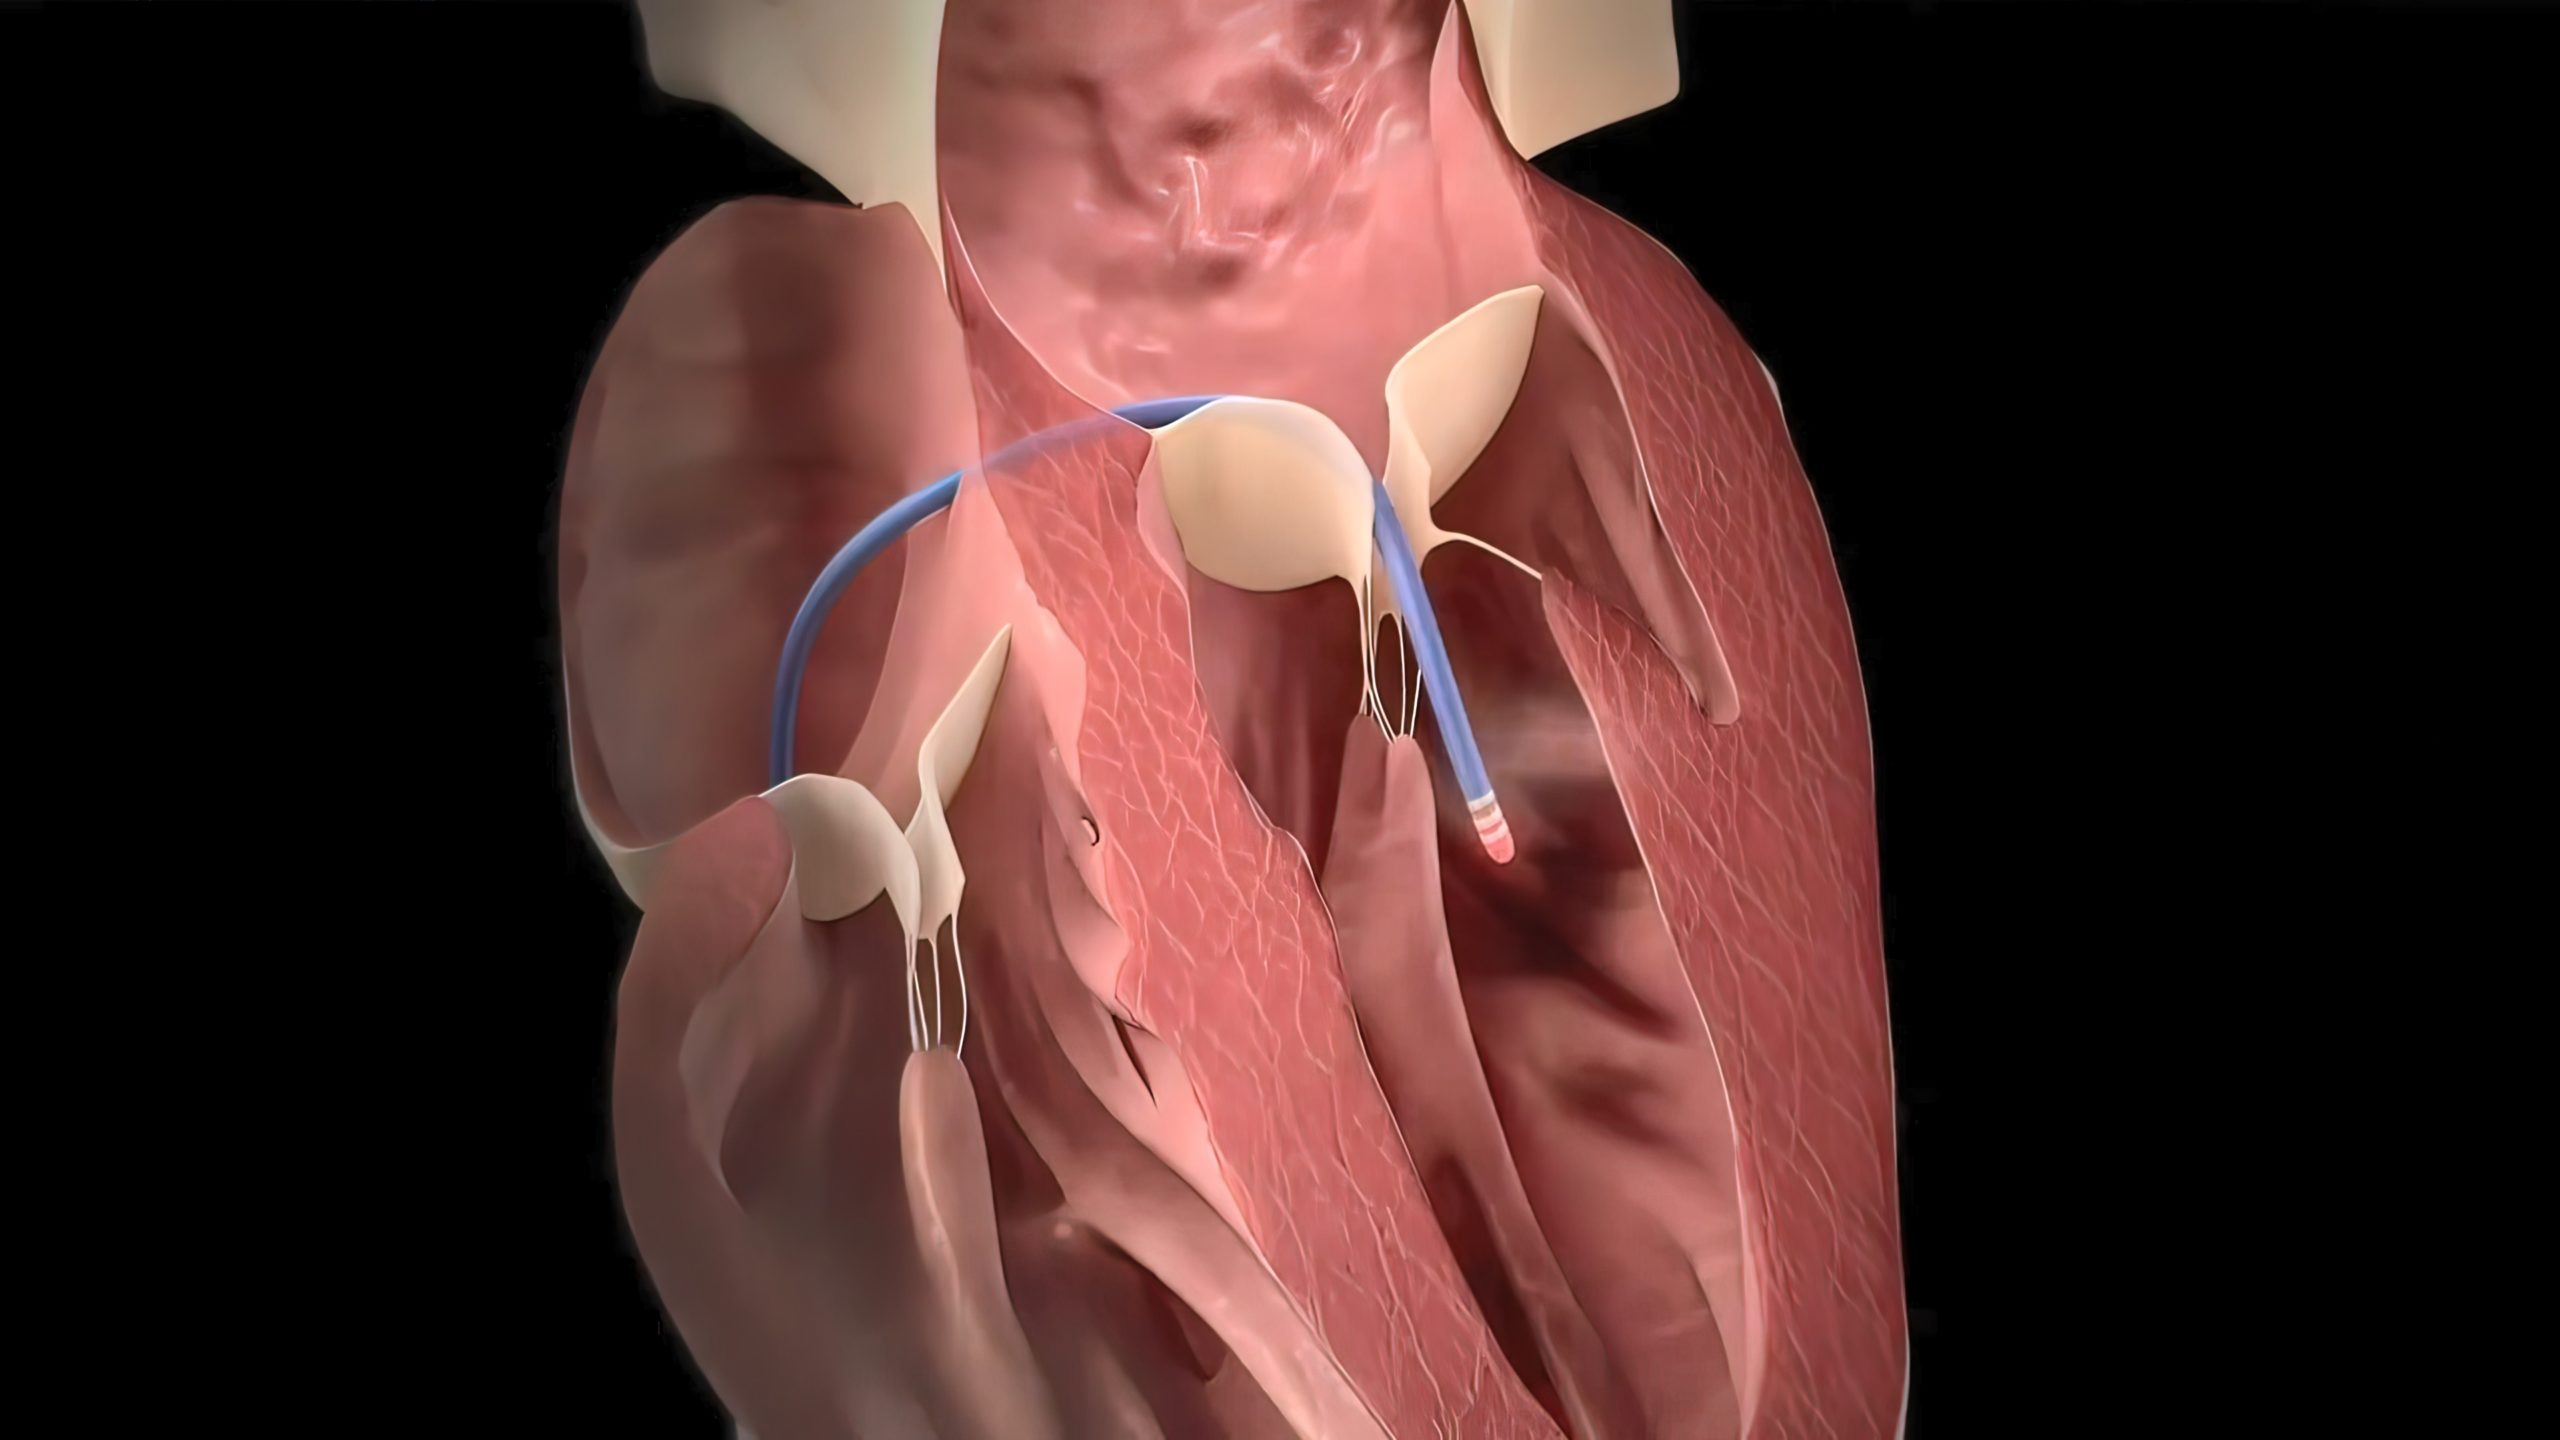

Holographic Therapy Guidance (HTG) is a new technology developed by EchoPixel that generates a real-time digital ...Patrick DalyAtrial Fibrillation | April 7, 2023